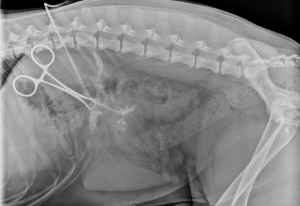

The next step for Luke was to perform some basic diagnostics including some radiographs (x-rays) of both his thorax (chest) and abdomen to rule out anything obvious or a communication from the outside into these body cavities. The x-rays were relatively unremarkable. With Luke under anesthesia just prior to surgery, a contrast study called a fistulogram was performed. A foley catheter was introduced into the non-healing wound and contrast fluid was injected. This fluid will show up white on x-rays. On this test, we were able to see some uptake of the contrast around an object in between the 11th and 12th rib. This test was very useful in showing us where we needed to focus our attention surgically.

The video pretty much says it all! On dissection in between the 11th and 12th rib (deep to the rib) we found a stick that was lodged there and it was successfully removed. This was a very gratifying surgery. You may be asking, were was the stick – which is an excellent question, did it come from the abdomen, chest, etc? If there was direct communication within the abdomen, then we would be concerned with a septic (infection) peritonitis and likewise if it were within the chest cavity we would be concerned with a pyothorax (infection in the chest cavity). To help us determine this, another foley catheter was introduced (after copious flushing) into the space that was occupied by the stick and everything else was closed around the catheter. Contrast was injected into the catheter and a x-ray taken which showed the contrast in the stomach and not in the body cavity. Sequential x-rays were taken which showed the contrast in the gastrointestinal tract and not outside.